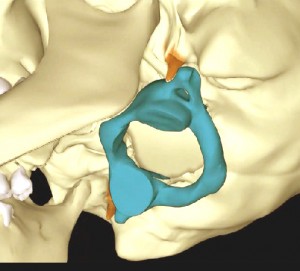

Az öreglyuk melletti bütykök elhelyezedése nem szimmetrikus, deformálódtak az idegek, erek csontos kijáratai és maga az öreglyuk is. Megdöbbentő bizonyítékot találtunk az atlasz koponyaalpot torzító elfordulására. Egy idős ember koponyáját alaposan megvizsgálva a következő tudományos bizonyítékot leltük: Az elfordult atlasz torzította és csontos átépülésre késztette a koponyaalap fontos alkotórészeit: az atlasszal ízesülő bütyköket, a koponyaalapról kilépő csontos csatornákat, […]]]>

Az öreglyuk melletti bütykök elhelyezedése nem szimmetrikus, deformálódtak az idegek, erek csontos kijáratai és maga az öreglyuk is. Megdöbbentő bizonyítékot találtunk az atlasz koponyaalpot torzító elfordulására. Egy idős ember koponyáját alaposan megvizsgálva a következő tudományos bizonyítékot leltük: Az elfordult atlasz torzította és csontos átépülésre késztette a koponyaalap fontos alkotórészeit: az atlasszal ízesülő bütyköket, a koponyaalapról kilépő csontos csatornákat, […]]]>

Súlyos testi és lelki panaszainak megoldását keresve René Claudius SCHÜMPERLI az 1993-1996-ig tartó intenzív kutatásai során rádöbbent arra, hogy a koponya-atlasz ízületben az Atlasz (első nyakcsigolya) szinte minden embernél ficamszerűen elfordult állapotban van. Megállapította azt is, hogy az atlasz elfordulását változó mértékű elbillenés is kíséri. Tehát a koponya alátámasztottsága nem vízszintes, és változó mértékű és súlyosságú egyensúlytalanság lép fel. A […]]]>

Súlyos testi és lelki panaszainak megoldását keresve René Claudius SCHÜMPERLI az 1993-1996-ig tartó intenzív kutatásai során rádöbbent arra, hogy a koponya-atlasz ízületben az Atlasz (első nyakcsigolya) szinte minden embernél ficamszerűen elfordult állapotban van. Megállapította azt is, hogy az atlasz elfordulását változó mértékű elbillenés is kíséri. Tehát a koponya alátámasztottsága nem vízszintes, és változó mértékű és súlyosságú egyensúlytalanság lép fel. A […]]]>